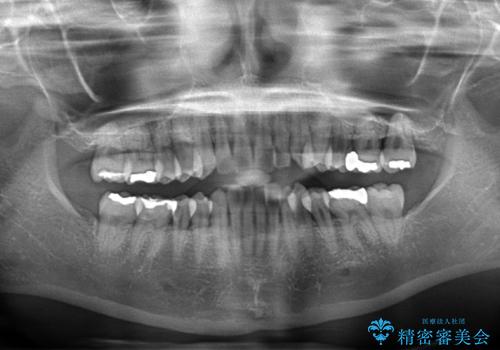

- 下顎の八重歯と、上下のクロスバイトを気にして来院された患者様です。

インビザラインを用い、下顎全体の後方移動、IPR(歯と歯の間を削る)と歯列全体を拡大させることで、歯並びを整えていくこととしました。